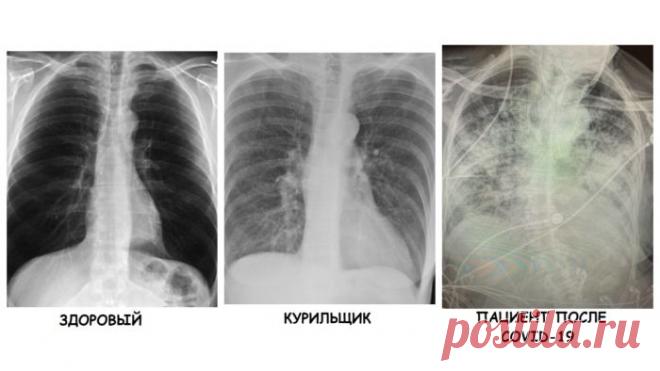

Врач сравнила рентген-снимки здорового, курильщика и больного коронавирусной инфекцией